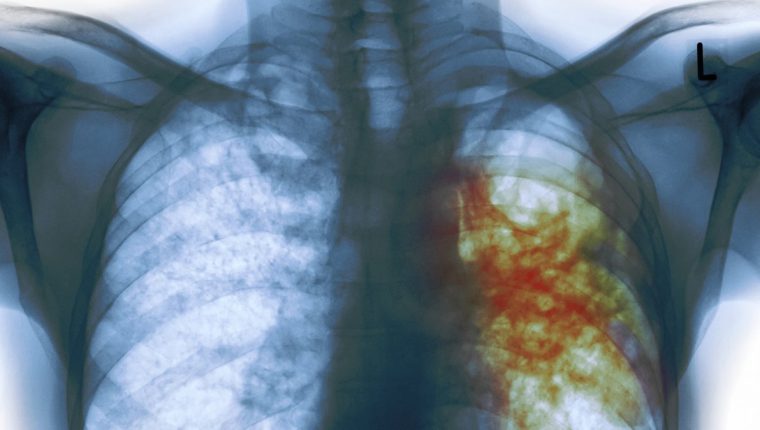

La trombosis se ha convertido en un padecimiento estrechamente ligado a las personas con Covid-19. (Foto Prensa Libre: Forbes)

Un riesgo está presente en las personas contagiadas del nuevo coronavirus SARS-CoV-2. La trombosis se ha convertido en un padecimiento estrechamente ligado a las personas con Covid-19 por las afectaciones ocasionadas por el virus en órganos como los pulmones y el corazón.

La trombosis es la formación de un coágulo en el interior de un vaso sanguíneo y es más frecuente su diagnóstico en las personas que padecen Covid-19, en comparación con otro tipo de infecciones.